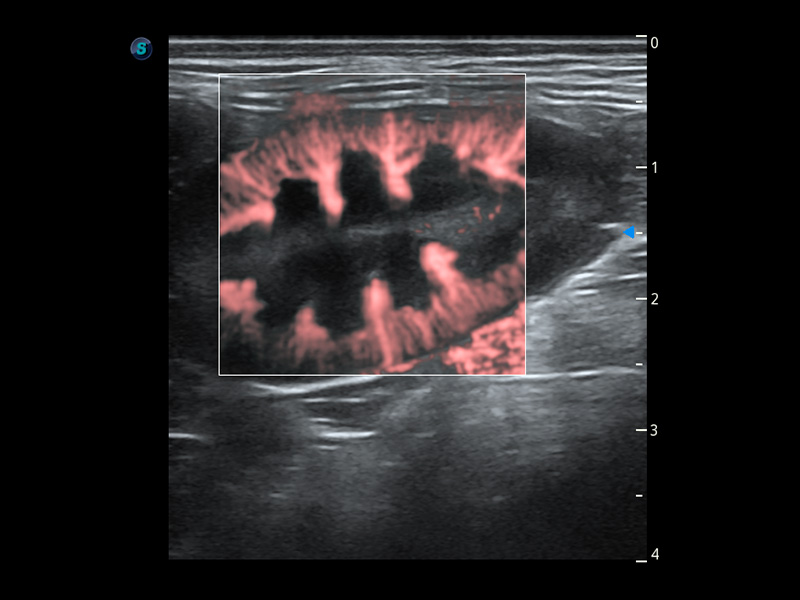

优异的基础图像

(犬)四腔心血流